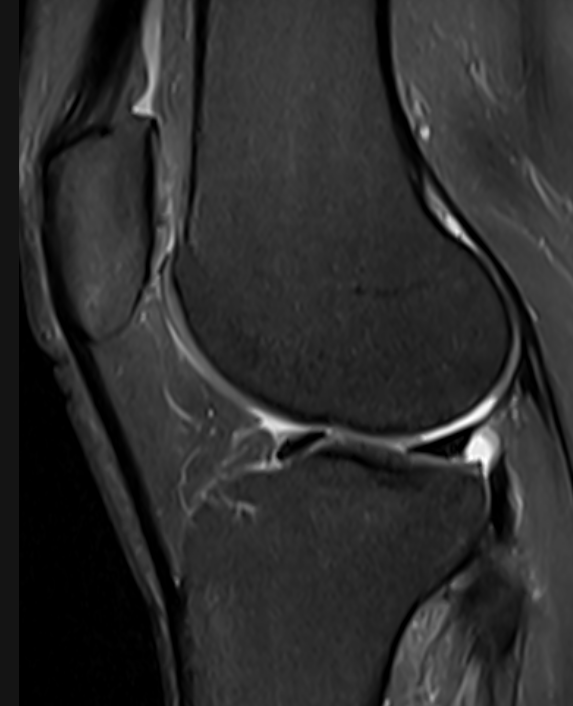

3. Cartilage defect